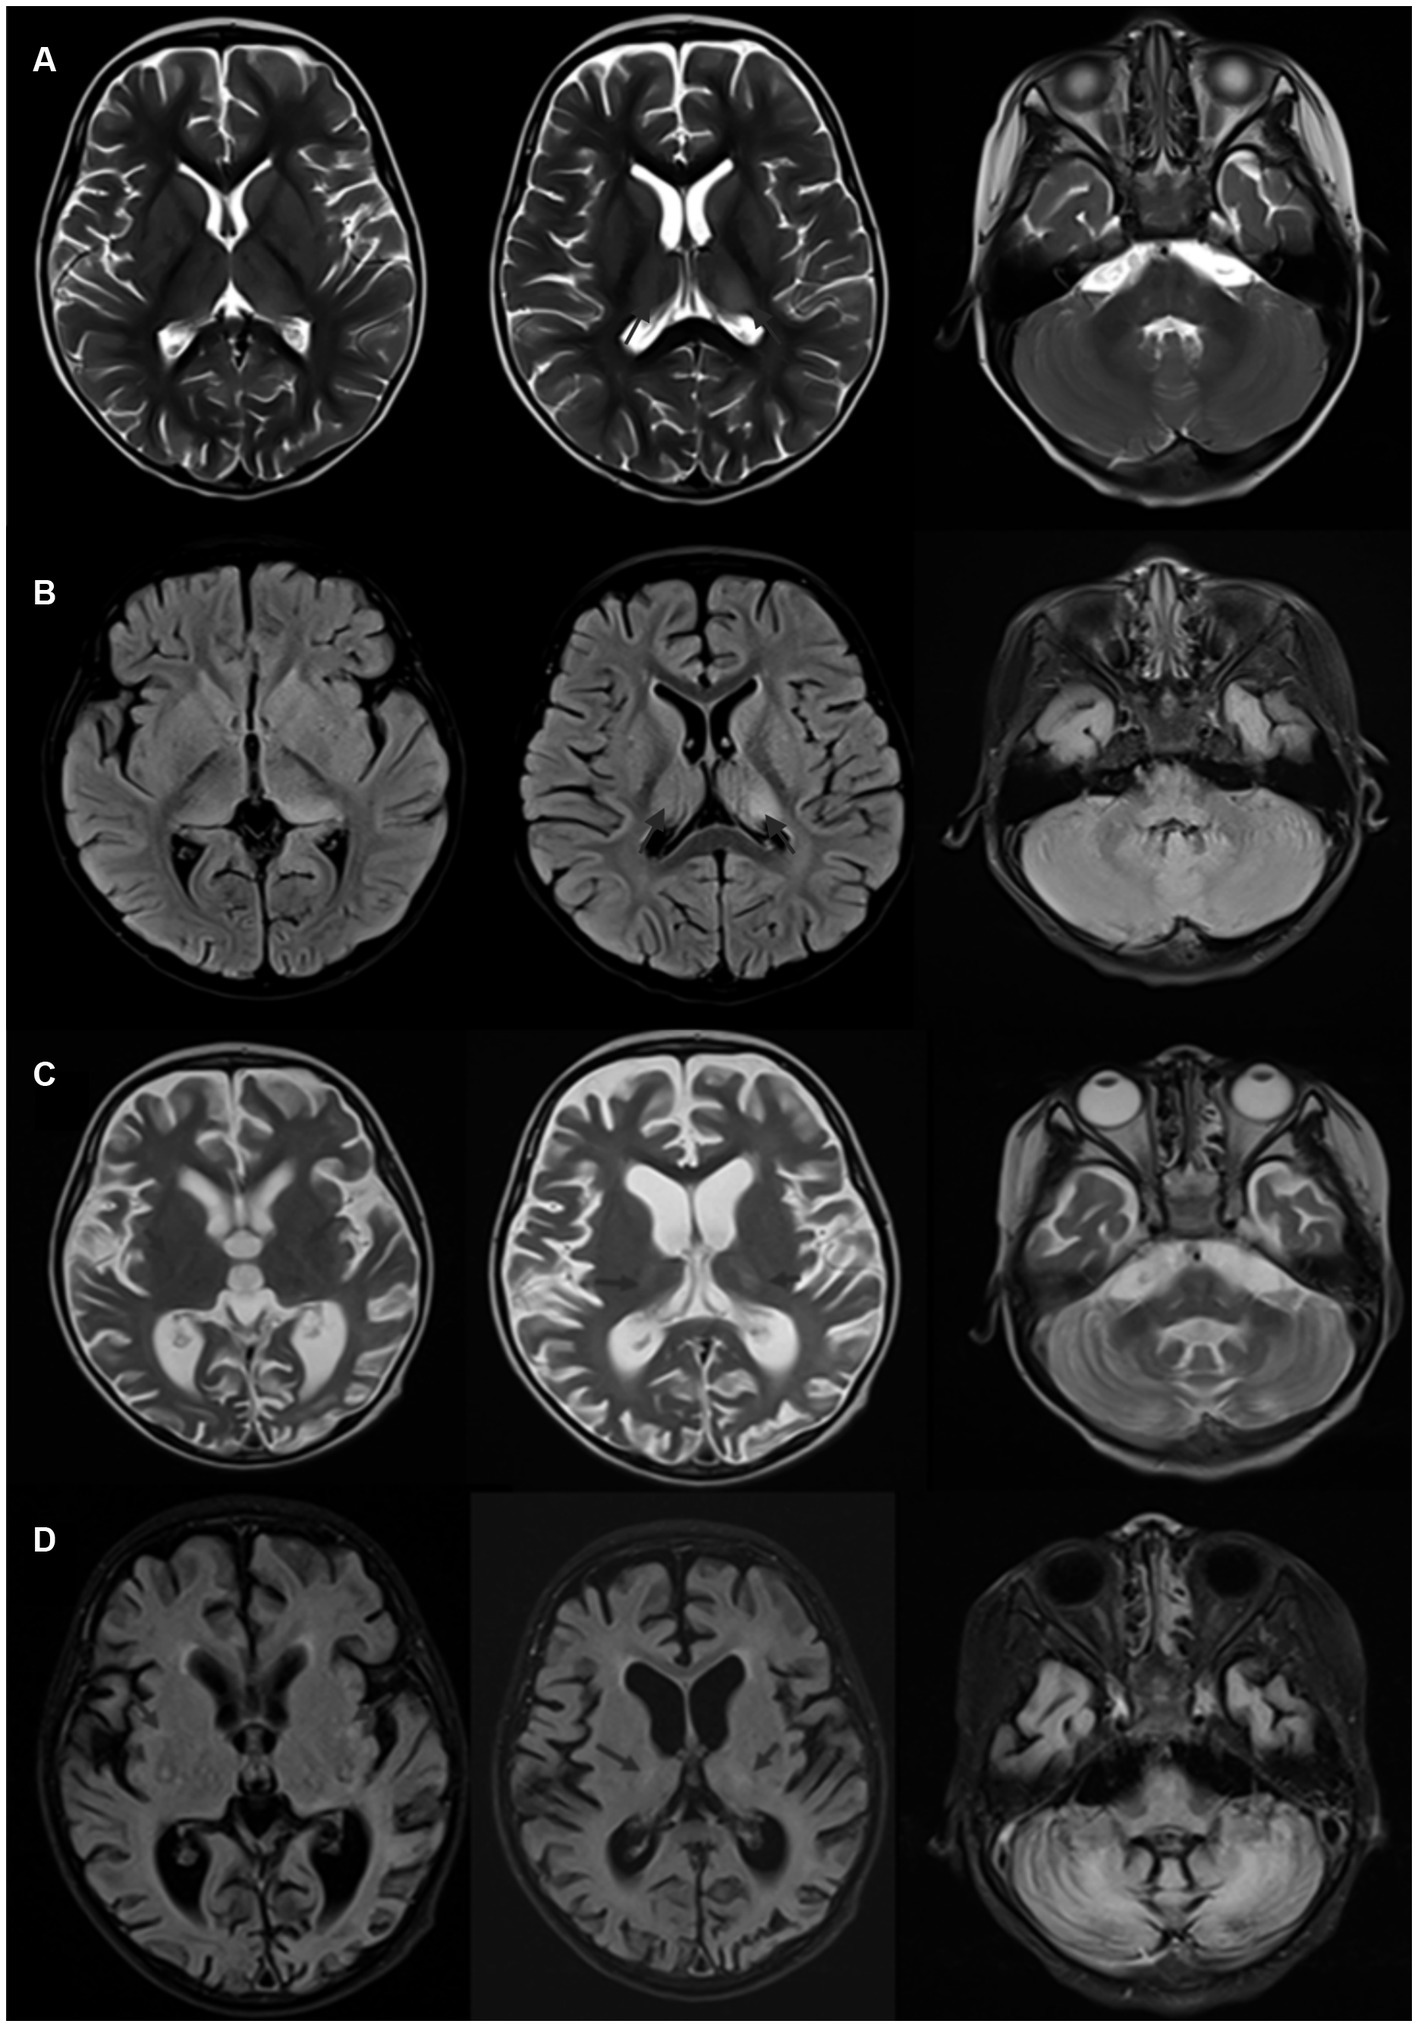

The modified Rankin Scale (mRS) was utilized to assess neurological disability at the peak of illness (maximum score) and during the final follow-up (terminal score). Patient 1 was followed up for three months, whereas Patient 2 was followed up for one year. Table 2 presents the treatment details and maximum/terminal mRS scores for both patients (see Figure 2).

Figure 2

(A,B) Brain MRI of Patient 2, acquired one week after onset, demonstrating T2 and FLAIR hyperintense signals in the basal ganglia, dorsal thalamus, and bilateral cerebellar hemispheres. (C,D) Brain MRI of Patient 2, obtained one year after onset, showing a reduction in the original lesions in the basal ganglia and dorsal thalamus, along with marked global cerebral atrophy and significant ventricular dilation.

Most patients with this condition have normal or nonspecific changes in cranial imaging. Gaig et al. (19) reported that 18 out of 22 patients had normal or nonspecific changes in Brain MRI, with others showing mild brainstem or bilateral hippocampal atrophy. Carles et al. (13) drew a similar conclusion, with 58 out of 70 patients showing normal or nonspecific changes in Brain MRI, 6 with brainstem atrophy, and 3 with cerebellar atrophy. The paediatric case reported by Ye et al. (14) showed meningeal enhancement on Brain MRI but no cerebral parenchymal lesions. In the two cases discussed in this article, Patient 1 had normal cranial imaging, while Patient 2 showed significant changes, with symmetrical abnormal signals in the bilateral cerebellar hemispheres, basal ganglia, and dorsal thalamus, and notable cerebral atrophy post-treatment. Cases with significant Brain MRI abnormalities have been reported, such as the case by Han et al. (21) showing symmetrical abnormal signals in the dorsal cerebrum and deep white matter of the cerebellum, including the upper part of the cerebellum and ventrolateral thalamus. Patient 2, who developed symptoms post-infection, had a young age of onset, acute onset, rapid progression, and symmetrical intracranial lesions. Despite thorough metabolic assessments and whole-exome sequencing, no evidence of a metabolic encephalopathy was found. The significant cerebral parenchymal changes observed might be associated with the poor response to immunotherapy and unfavorable prognosis.